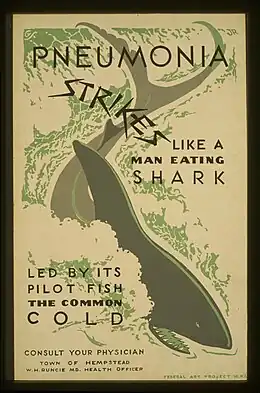

The common cold or the cold is a viral infectious disease of the upper respiratory tract that primarily affects the respiratory mucosa of the nose, throat, sinuses, and larynx.[6][8] Signs and symptoms may appear fewer than two days after exposure to the virus.[6] These may include coughing, sore throat, runny nose, sneezing, headache, and fever.[3][4] People usually recover in seven to ten days,[3] but some symptoms may last up to three weeks.[7] Occasionally, those with other health problems may develop pneumonia.[3]

| Complications | Usually none, but occasionally otitis media, sinusitis, pneumonia and sepsis can occur[5] |